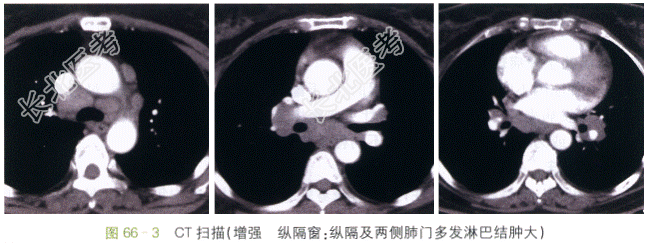

CT扫描肺窗示两肺门增大,肺门旁纹理结构紊乱,可见多个微小点状致密影,沿支气管血管束分布的增厚片状影,叶间裂下明显,可见少量纤维条索。纵隔窗示纵隔内、血管气管旁见大量肿大淋巴结,两侧肺门肿大的淋巴结呈对称分布;增强后可见淋巴结均匀强化,部分可见融合,邻近组织结构受压、移位。